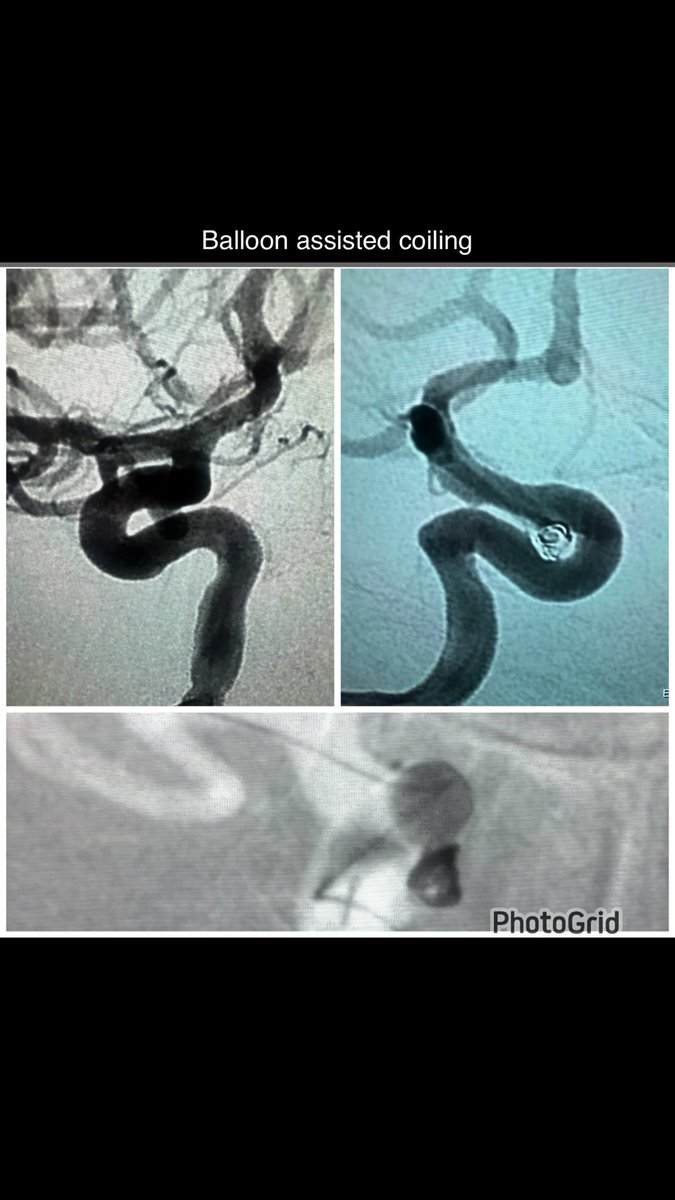

High-grade, concentric calcified internal carotid artery stenosis successfully managed with carotid artery baloon angioplasty wiyh stenting through transradial approach. Despite complex plaque morphology, optimal luminal restoration achieved.#Neurointervention #StrokePrevention

High-grade, concentric calcified internal carotid artery stenosis successfully managed with carotid artery  baloon angioplasty wiyh stenting through transradial approach.

Despite complex plaque morphology, optimal luminal restoration achieved.#Neurointervention #StrokePrevention